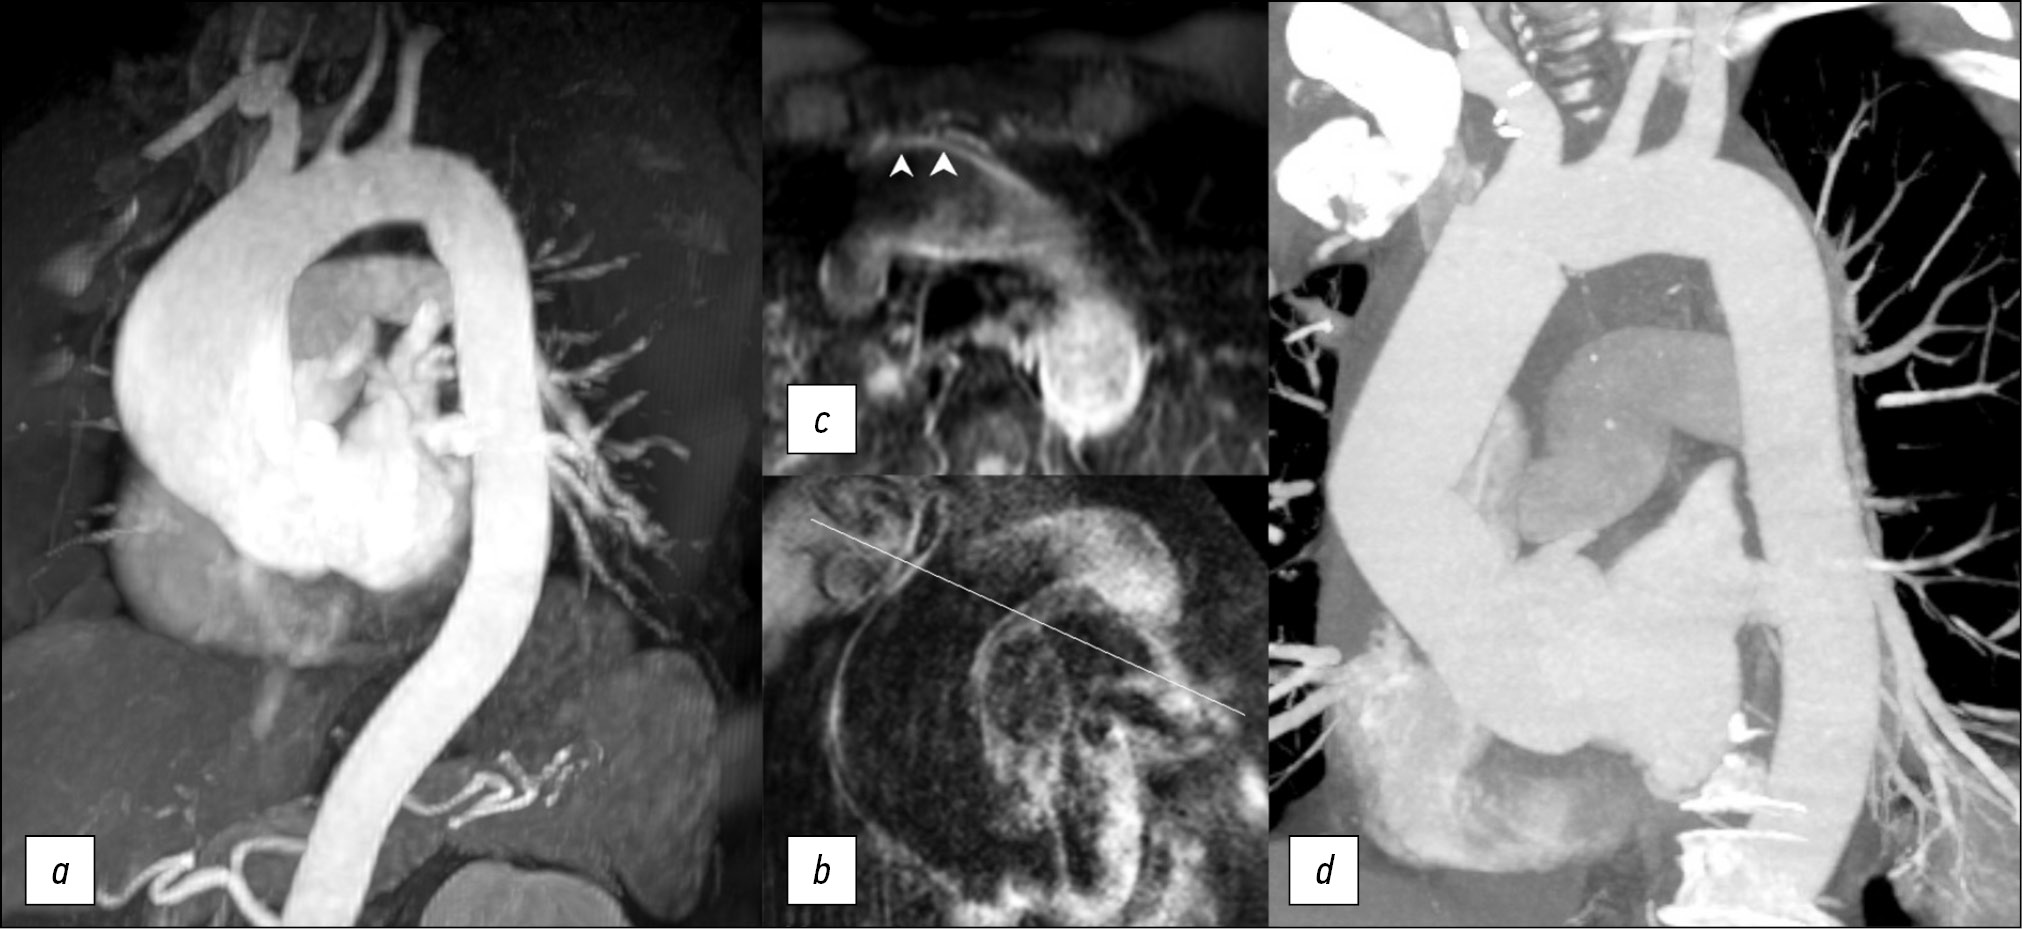

MRI数据显示,患者升主动脉从根部扩张 至9 cm长,最大直径为5.5 cm。动脉瘤定位区域的主动脉壁均匀变细,中部更为明显,搏动减弱,有运动障碍迹象,从动脉瘤囊边缘到头臂干主动脉壁完整不超过3 cm(见图2),主动脉直径在此水平不超过3.5 cm。还应该注意患者的二瓣叶型主动脉瓣。

图2。对比增强磁共振血管造影,动脉期,屏气,斜投影,主动脉3D重建(a); 在升主动脉瘤远端边缘的“黑血”模式下轴位的T1-SPIR(b);在斜投影中的头臂干口的前面(c)。完整的主动脉壁(箭头),手术治疗后胸主动脉的计算机断层扫描血管造影(d)。

根据现代建议[1,2,4],患者需要手术治疗。未检测到胸主动脉壁及其主要分支的近端部分的解剖、增厚和血管增生。主要分支口的解剖结构是典型的。

最初,计划在头臂干孔口前直接应用夹子,但根据核磁共振成像的结果调整了手术方法。考虑到动脉瘤远端的主动脉壁病变的普遍性,决定在循环停止和前向单侧脑灌注的情况下进行干预。值得注意的是,随着主动脉壁的切除和病理变化,在术后早期和后期都可能出现并发症。在这个病案中,患者接受了升主动脉和主动脉弓的冠状动脉上修复术,并形成了半弓型远端吻合。

手术治疗后,患者接受了胸主动脉CT血管造 影(见图2)。术后图像显示,对比主动脉腔的直径没有扩张,也没有内漏的现象。